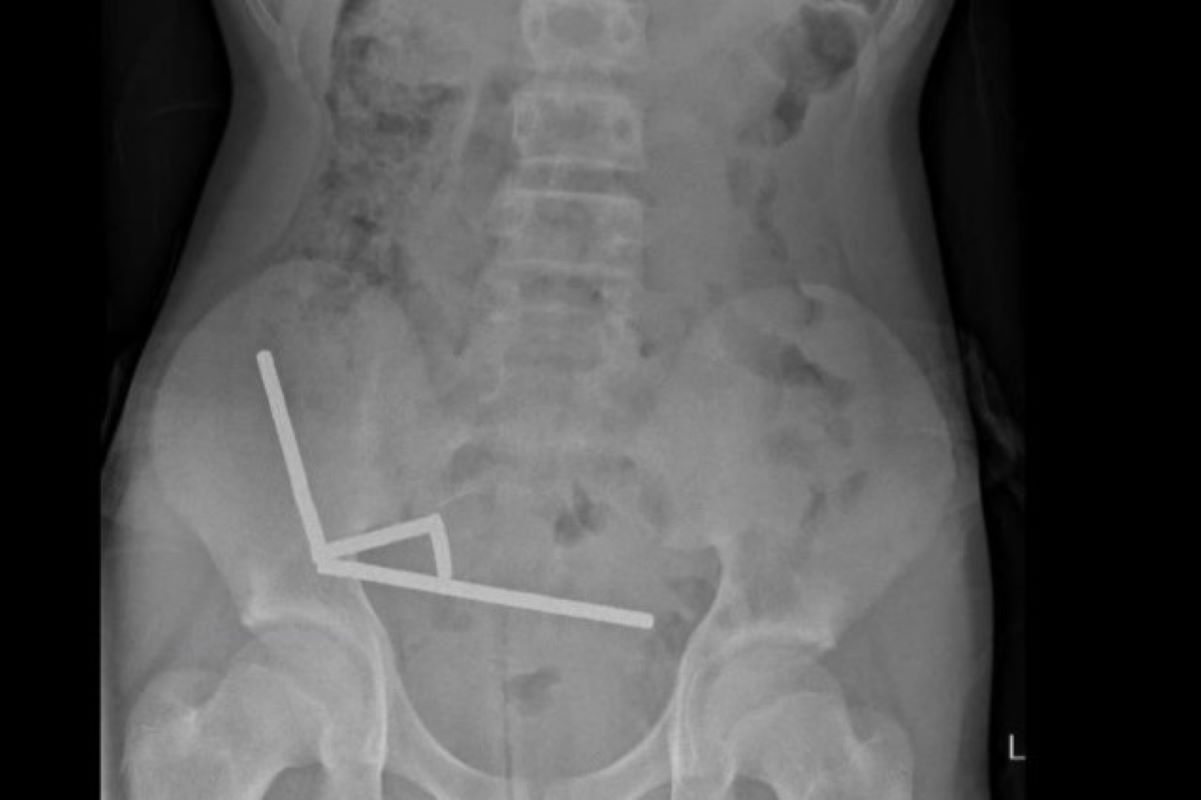

Os exames mostraram que os ímãs haviam se agrupado em quatro correntes dentro do abdômen, unindo diferentes partes do intestino. A forte atração magnética fez com que o órgão sofresse necrose por pressão, quando o tecido morre por compressão prolongada, o que exigiu uma cirurgia imediata.

Durante o procedimento, os cirurgiões conseguiram remover os ímãs, mas parte do intestino delgado e grosso precisou ser retirada. O adolescente permaneceu hospitalizado por oito dias até receber alta.